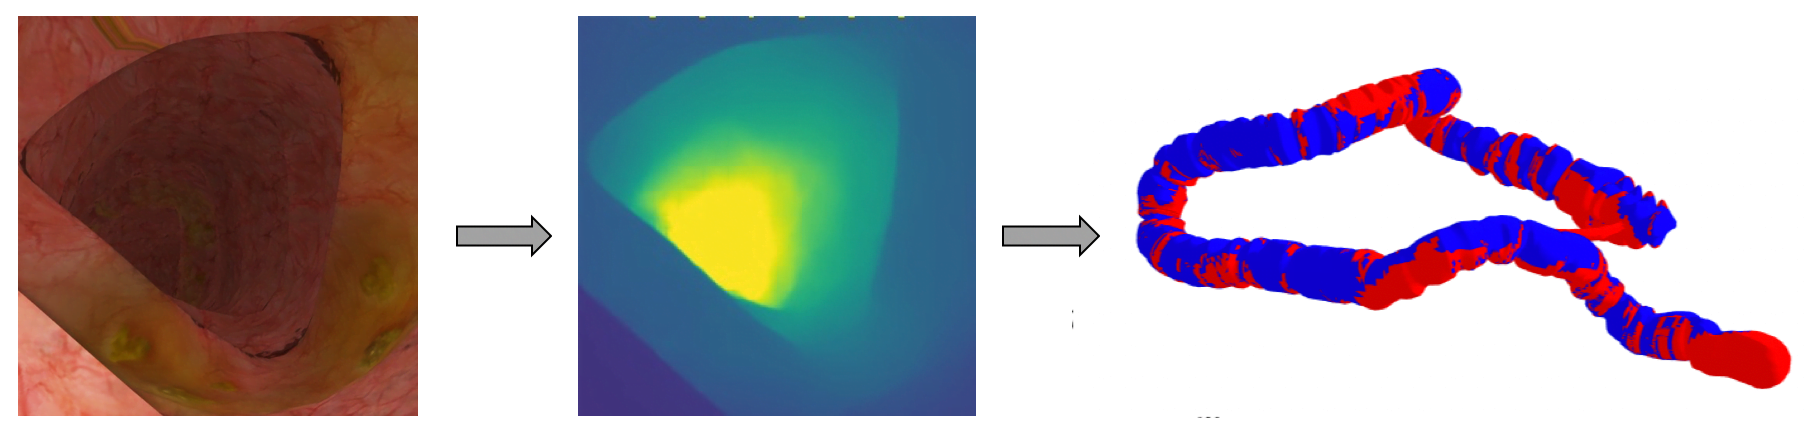

Google kombiniert 3D-Modell des Darms und Bildanalyse

In ihrer Forschungsarbeit "Detection of Elusive Polyps via a Large Scale AI System" präsentieren die Forscher ihren zweiteiligen Ansatz: Das erste KI-System erstellt während der Darmspiegelung Tiefenaufnahmen, rekonstruiert daraus ein 3D-Modell des untersuchten Darms und visualisiert untersuchte und noch nicht gesichtete Bereiche direkt im Modell. Gastroenterologen können so direkt sehen, welche Darmareale noch nicht diagnostiziert sind.